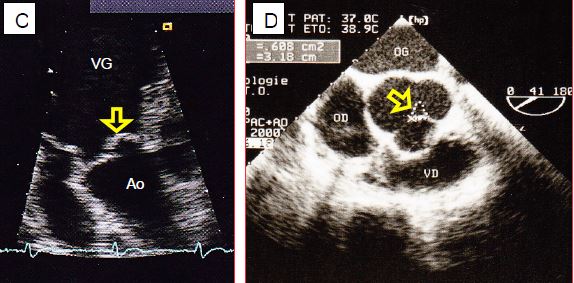

Figure 11.135 : Images bidimensionnelles d’insuffisance aortique. A : hauteur normale de coaptation des cuspides aortiques. B : prolapsus de la cuspide coronarienne droite. C : prolapsus de la cuspide non-coronaire en vue transgastrique. D : orifice de régurgitation central lors de dilatation de l’anneau ; la surface de l’orifice (0.6 cm2) signe une IA sévère.